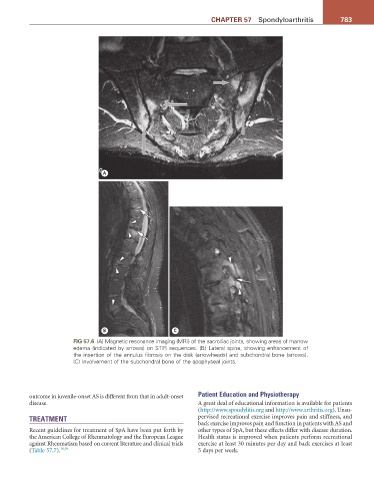

FiG 57.6 (A) Magnetic resonance imaging (MRI) of the sacroiliac joints, showing areas of marrow

edema (indicated by arrows) on STIR sequences. (B) Lateral spine, showing enhancement of

the insertion of the annulus fibrosis on the disk (arrowheads) and subchondral bone (arrows).

(C) Involvement of the subchondral bone of the apophyseal joints.